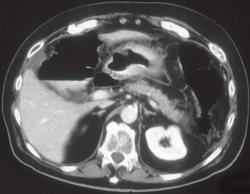

Gastric Carcinoma at Anastomosis of Stomach and Small Bowel